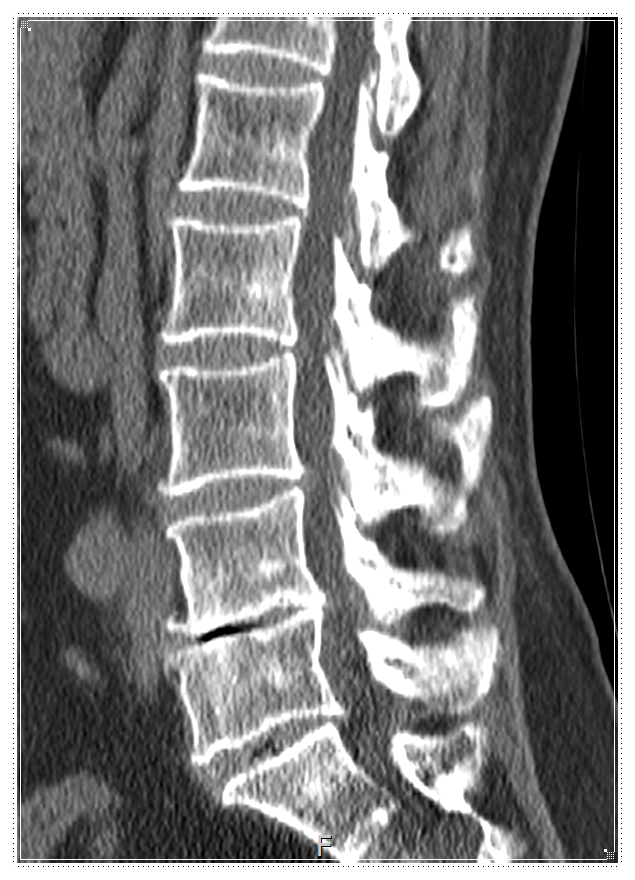

![]()